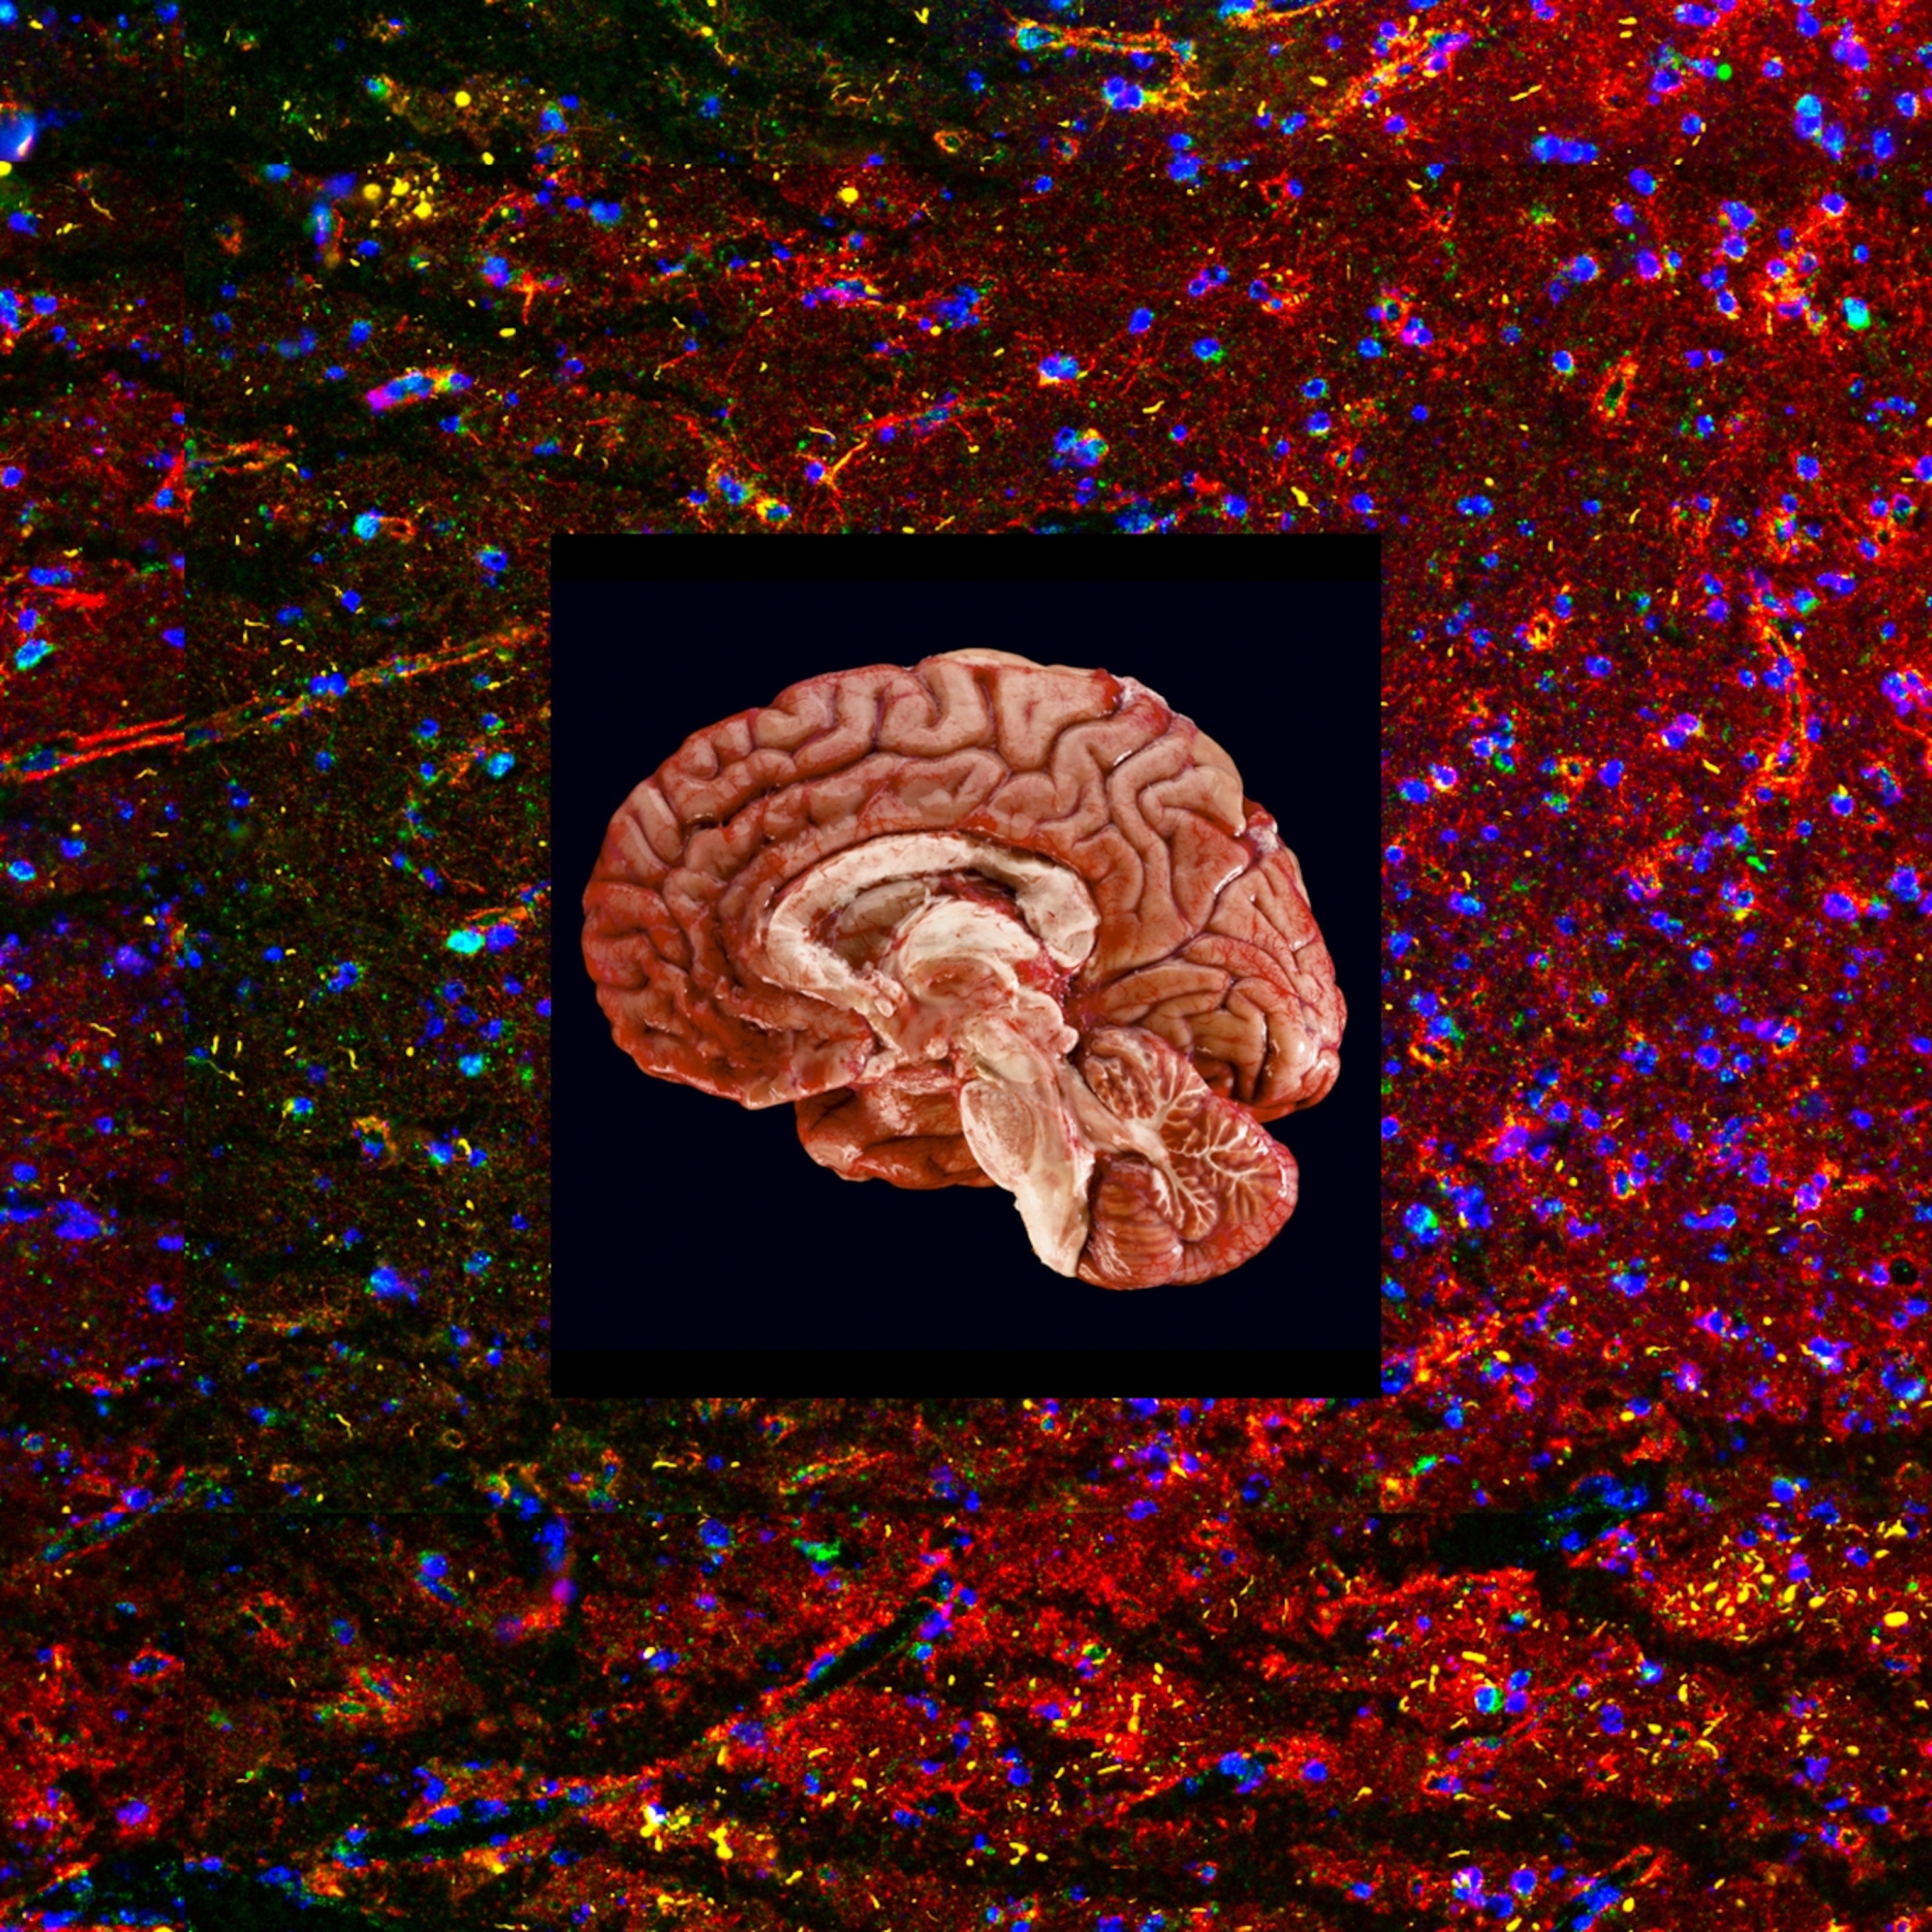

But both decisions are highly controversial. The approvals were not based on the drugs’ impact on disease progression, but on their ability to remove abnormal clumps—plaques—of a toxic form of a protein called beta amyloid that aggregates in the brains of Alzheimer’s patients, which were thought to be the underlying cause of the disease. Also, the drugs are expensive, can cause adverse side effects, and may have modest benefits, at best, in preserving brain function as the disease progresses. Some experts argue that the treatment benefits don’t clearly outweigh the risks.

Both lecanemab and aducanumab (marketed as Aduhelm), which the FDA approved in 2021, are monoclonal antibodies—laboratory manufactured proteins—designed to target and remove the beta amyloid plaques that are believed to trigger the disease. While aducanumab binds more strongly to insoluble forms of beta amyloid, lecanemab targets a soluble version called a protofibril, which is thought to be more toxic to neurons.